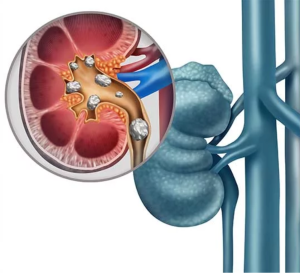

حصوات الكلى او بالانجليزيه (Kidney Stones) وهي عبارة عن قطع صلبة تشبه الحصى تتشكّل في إحدى كليتيك أو كلتيهما عند وجود مستويات عالية من بعض المعادن في البول.

تختلف حصوات الكلى في الحجم والشكل. قد تكون صغيرة مثل حبة الرمل أو كبيرة مثل حبة البازلاء. نادرا ما تكون بعض حصوات الكلى بحجم كرات الجولف. قد تكون حصوات الكلى ملساء أو خشنة، وعادة ما تكون صفراء أو بنية اللون.

فرط أوكسالات البول الأولي (PH) هو مرض وراثي نادر يسبب زيادة تراكم مادة تسمى “الأوكسالات” في الجسم. تتحد هذه الأوكسالات مع الكالسيوم في الكلى لتشكيل بلورات يمكن أن تلتحم معًا لتكوين حصوات في الكلى، أو تترسب داخل أنسجة الكلى، مما يُسبب التلف التدريجي للكلى الذي قد يصل في النهاية إلى الفشل الكلوي والحاجة لغسيل الكلى.

●تكلس الكلى (العثور على بلورات في أنسجة الكلى عند فحصها).